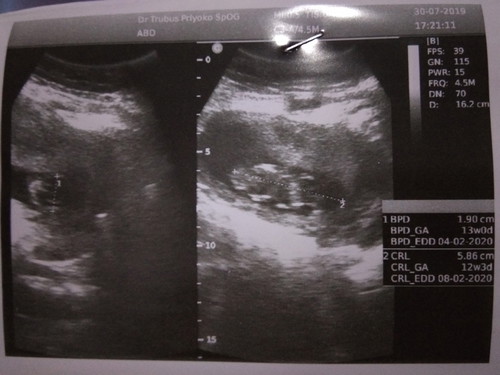

Hey bunda Yang waktu sebulan lalu aku divonis kemungkinan besar kehamilanku ini BO karna 8week belum nampak janin Alhamdulillah hasil usg kmarin bikin excited bgt☺ bayi ku udah terlihat usia nya pun sesuai sama hitungan dari HPHT pas 12week, sudah lengkap dari lengan, kaki, ukuran kepala, panjang janin normal semua❤ makasih bunda untuk semangatnya, aku banyak belajar dari para bunda yang hebat disini love u?